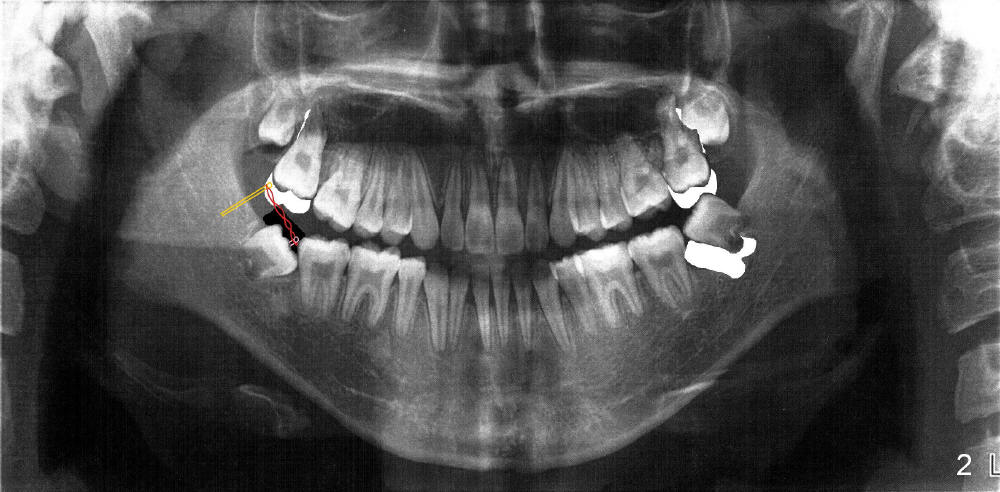

最好方法(不拔除下颌智齿,图二):同样需要做intrusion,同时也使用微型植牙,植在下颌第二磨牙远中(黄色),切开埋伏智齿表面牙龈(黑色),在智齿合面固定一个固定装置(lingual

button, 粉红色),在微型植牙和lingual

button之间挂上橡皮筋(power chains,红色),在持续引力下,智齿最终会移到适当位置,与上颌第二磨牙建立咬合关系(图二:十七号牙处,示意图)。